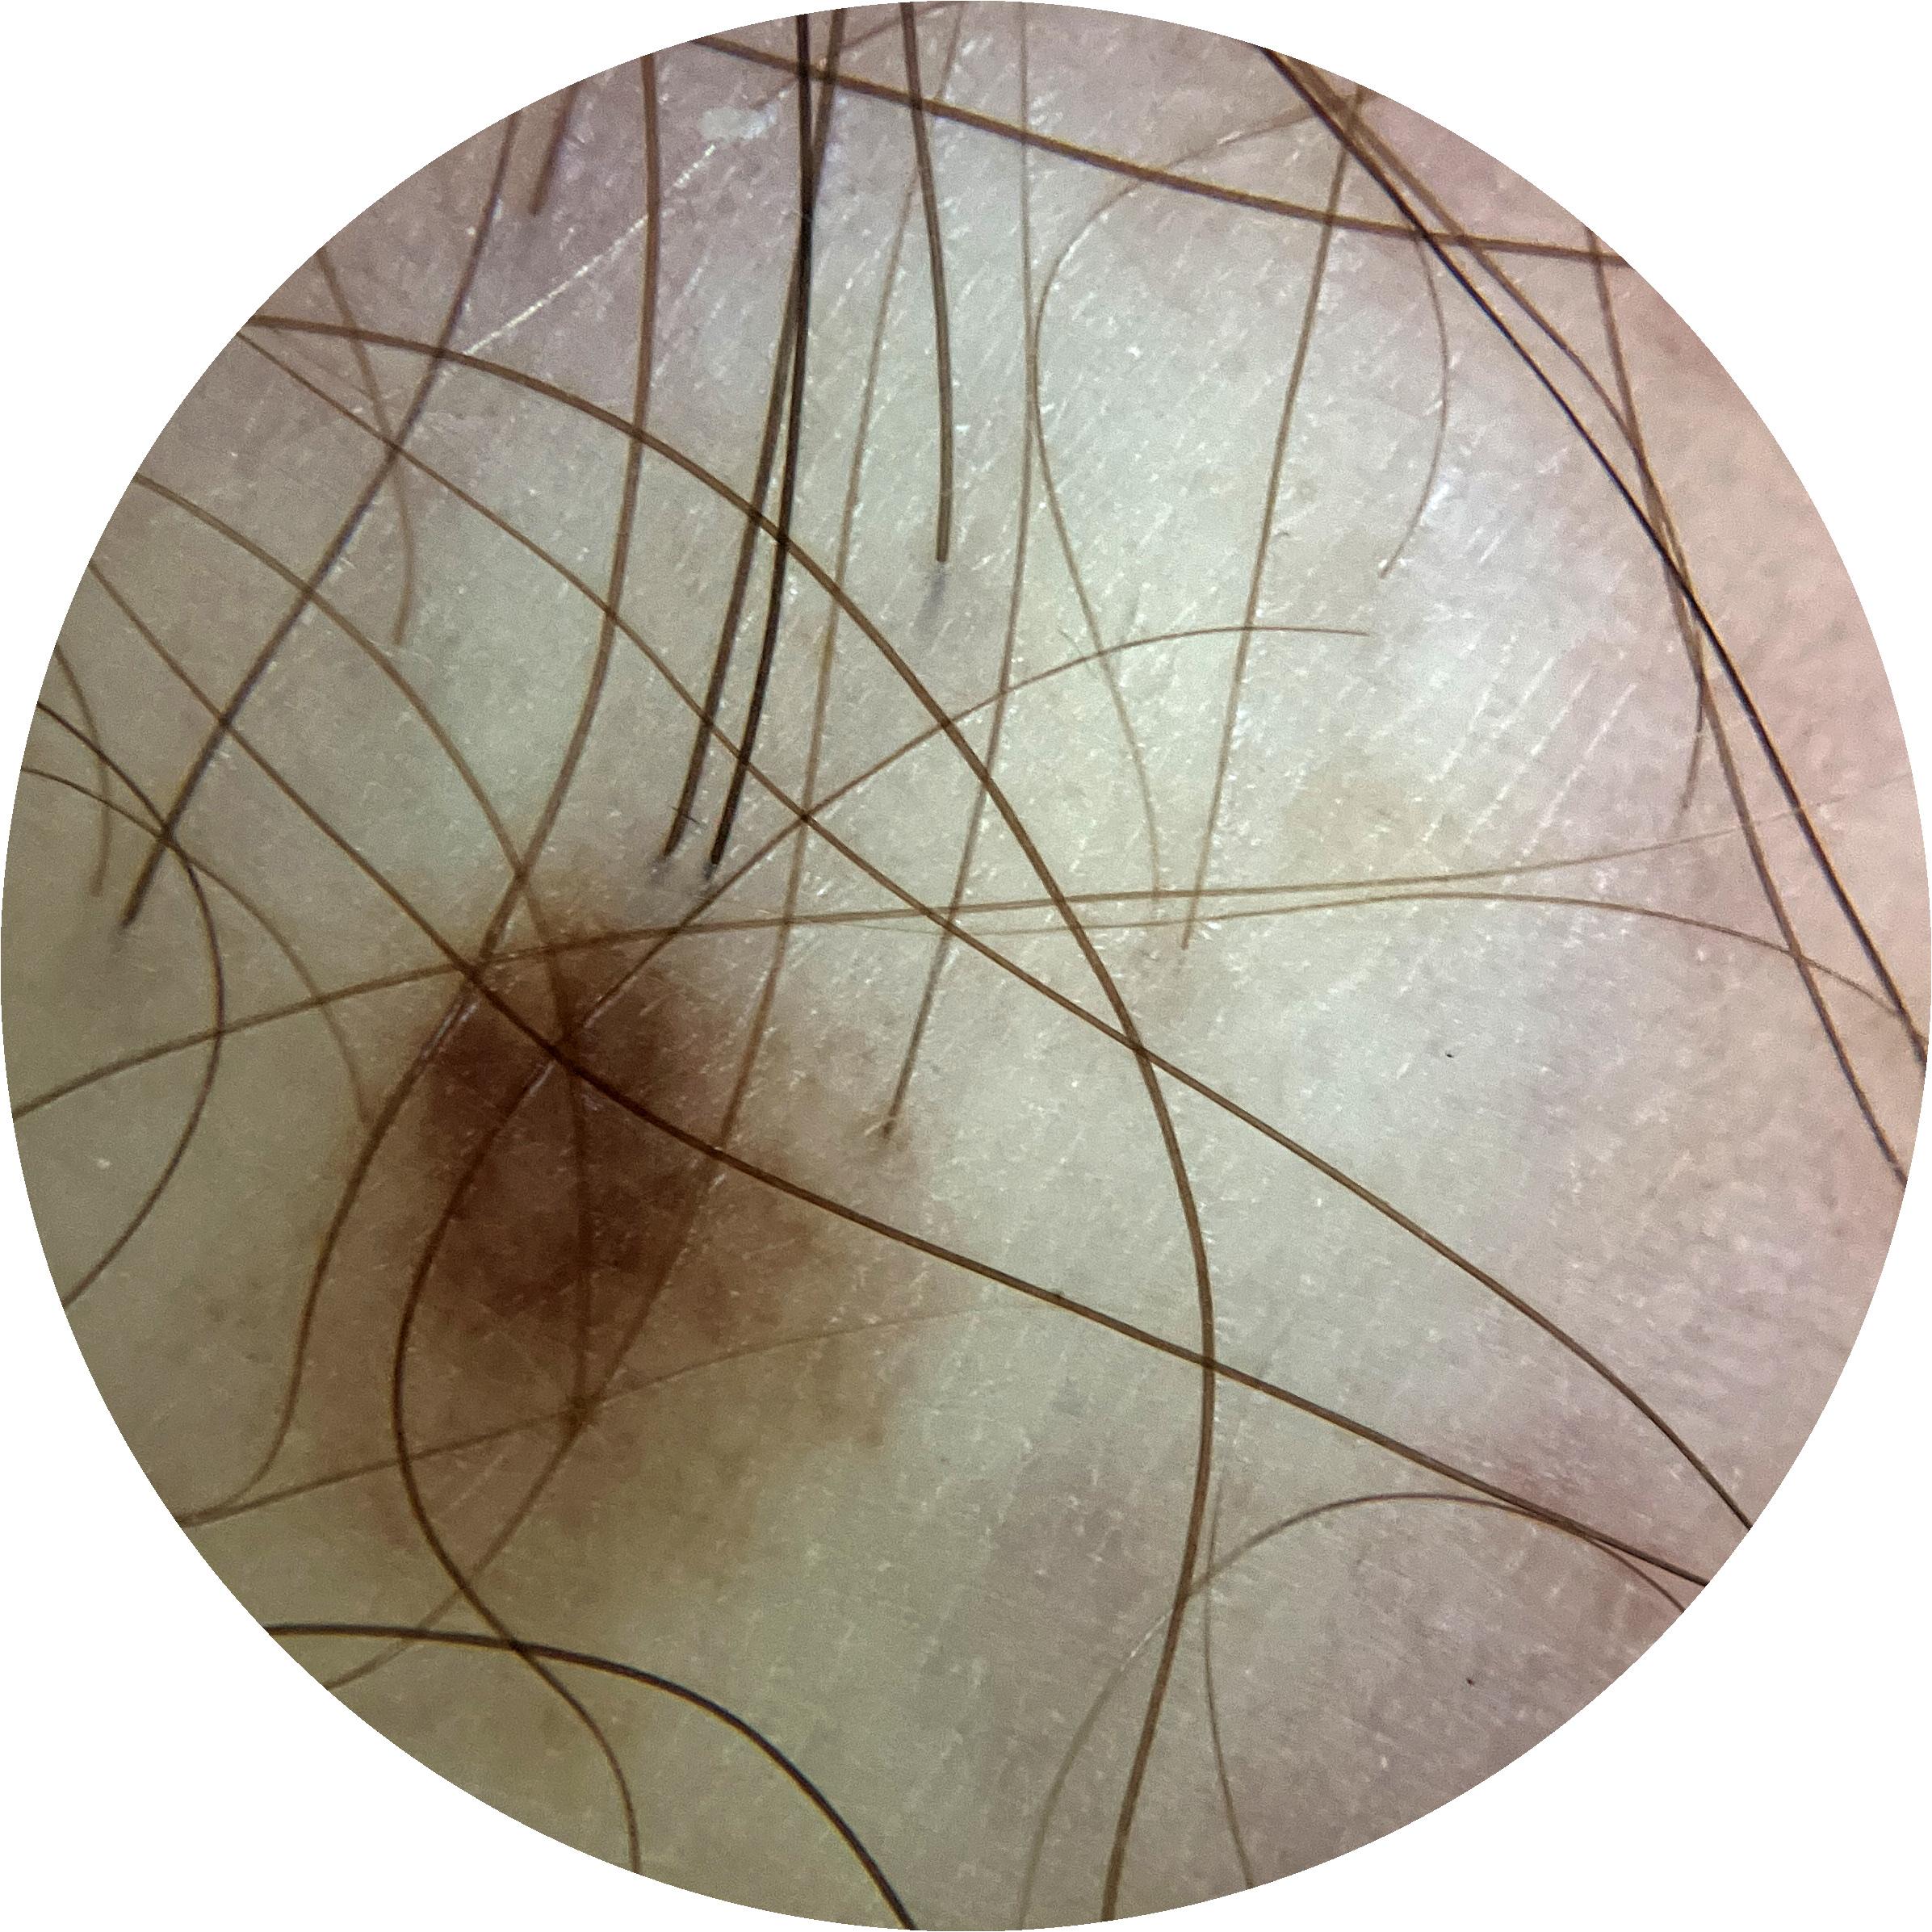

ISIC_8917580

Clinical

Field Value

acquisition_day 361

age_approx 60

anatom_site_1 Lower extremity

anatom_site_general lower extremity

concomitant_biopsy False

diagnosis_1 Benign

diagnosis_confirm_type single image expert consensus

family_hx_mm True

image_manipulation instrument only

image_type dermoscopic

lesion_id IL_4139461

patient_id IP_1989106

personal_hx_mm True

sex male